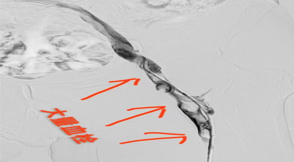

血栓的歸處

之前我們通過(guò)多篇文章做了關(guān)于血栓類(lèi)疾病的科普,一起認(rèn)識(shí)了血栓形成的危險(xiǎn)因素、形成過(guò)程及各種預(yù)防和治療措施等。所以大家就好奇血栓最后去了哪里,...